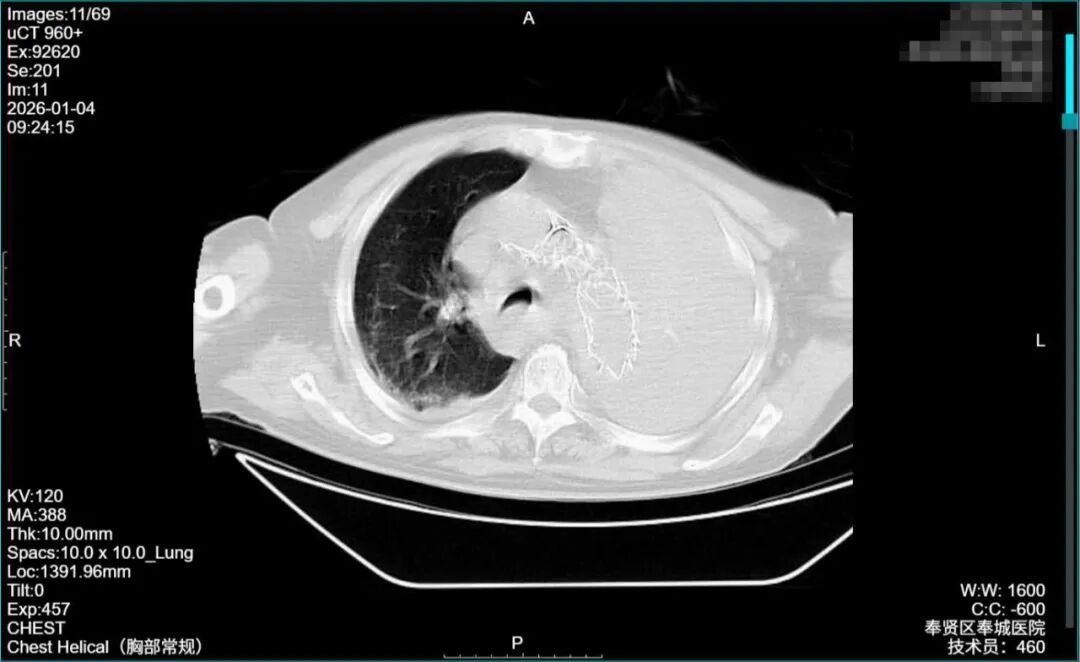

急诊团队凭借多年急危重症救治经验,瞬间判断这绝非普通胸痛!“立刻启动紧急救治绿色通道!”随着指令下达,吸氧、补液、心电监护等一系列生命支持措施同步进行。在患者血压极不稳定、无法长时间耐受检查的情况下,影像科团队火速到位,急诊增强CT血管成像(CTA)仅用15分钟就锁定“元凶”:主动脉夹层(StanfordB型)破裂!血液已涌入纵隔及左侧胸腔,形成巨大血肿,如同“血管破了个大洞”,每分每秒都在吞噬生命。

术后影像显示:覆膜支架定位精准,主动脉破口被完全隔绝,血管血流恢复正常!